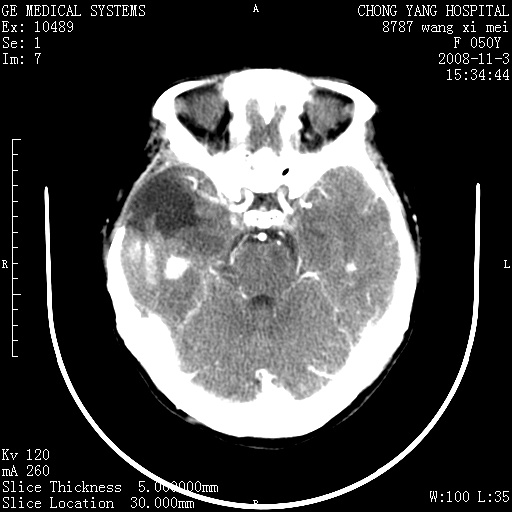

标题: CT16469:女,50岁,胶质瘤术后6年,今平扫加增强,请大家帮 [打印本页]

标题: CT16469:女,50岁,胶质瘤术后6年,今平扫加增强,请大家帮

右颞骨局限性缺如,局部脑组织无外隆。右颞叶可见片状脑脊液样低密度影,边缘较清,右侧侧脑室三角区可见一块状等密度影,且伴有强化,余未见明显异常改变。

考虑:右大脑术后改变伴肿瘤复发。

应考虑肿瘤复发,右颞顶叶已出现轻度强化肿块.必要时可与原片比较以下.

右侧颞顶部混杂密度影,内有钙化,有占位效应。应该是复发灶。结合术后片更好。

局部软化灶并钙化;无花边样强化,不象复发